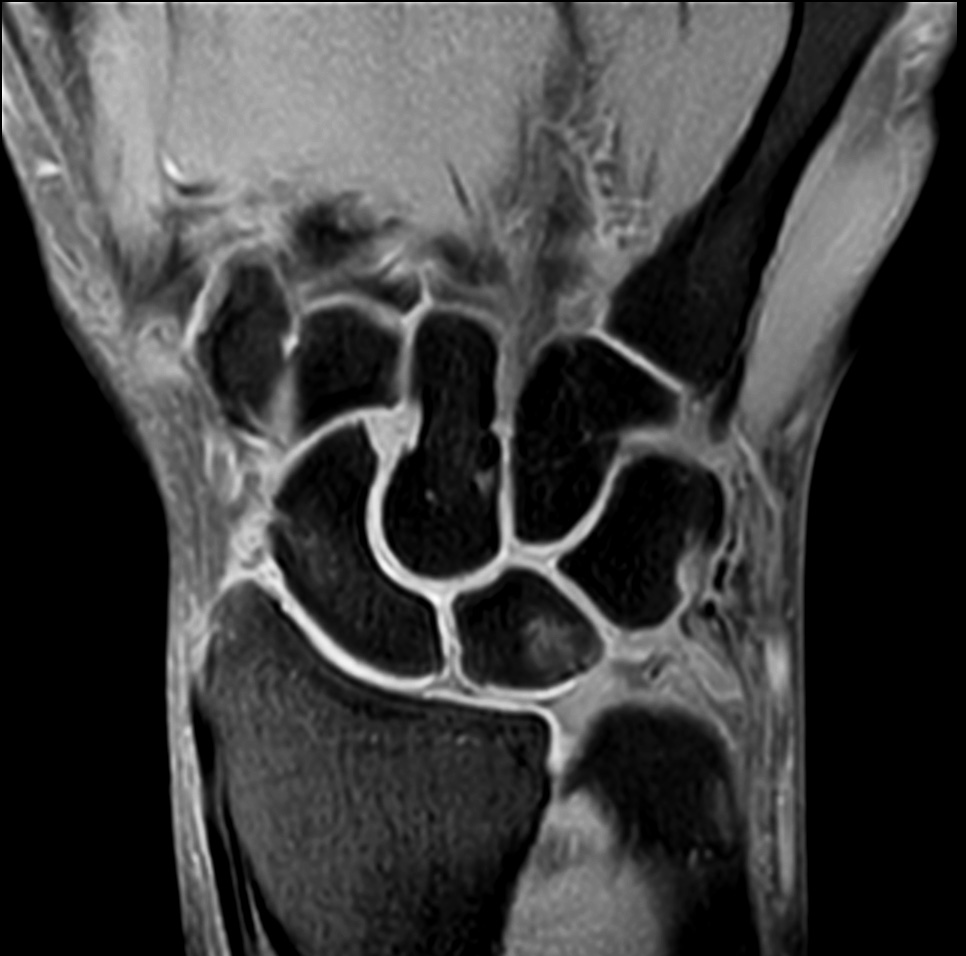

Comprehensive wrist imaging